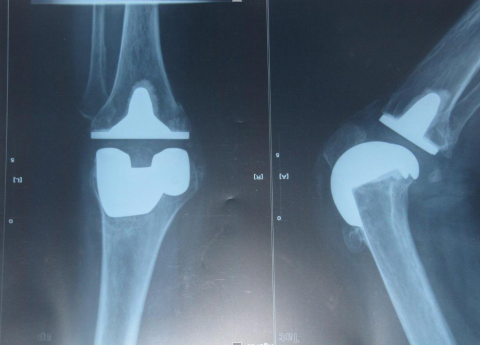

膝關(guān)節(jié)假體

術(shù)后復(fù)查X線片